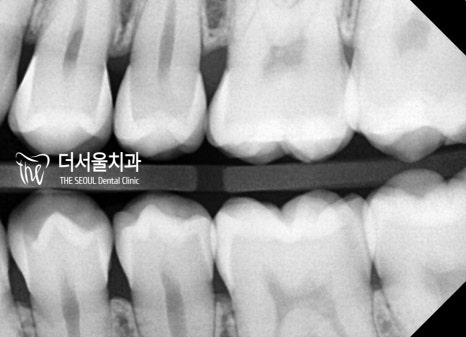

【 마무리 】

모든 치료가 마무리된 모습을 살펴볼까요?

이전과는 달리 훨씬 안정적인 모습의

맞물림이 관찰되고 있습니다.

교합은 물론이며 더욱 긴밀한 배열을

갖게 된 것을 볼 수 있는데요.

심미적으로나 기능적으로나

환자께서 좋아하실 수 있는 결과를 안겨드리게 되어